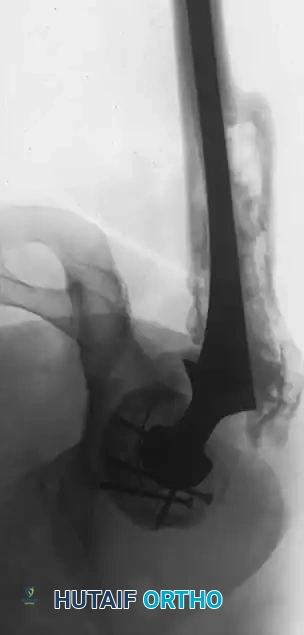

Associated Surgical & Radiographic Imaging